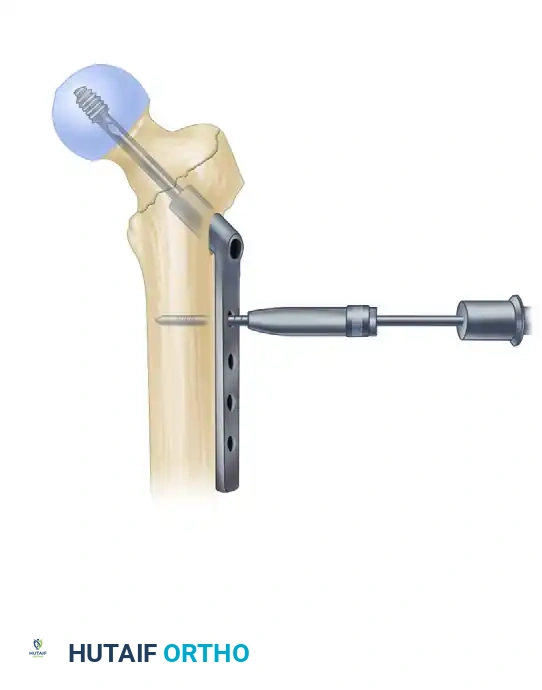

5. Lag Screw Placement and Compression

Achieving optimal lag screw placement is the most critical factor in preventing mechanical failure (cut-out). The goal is a Tip-Apex Distance (TAD) of less than 25 mm.

- Evaluate Version: Check the version of the nail on the lateral fluoroscopic view. The version is correct when the nail, the drill guide, the femoral neck, and the femoral head are all perfectly collinear.

- Make a small stab incision laterally through the skin and fascia lata corresponding to the targeting guide. Place the appropriate drill sleeve assembly down to the lateral cortex of the femur.

- Advance a threaded guide pin through the sleeve, up the femoral neck, and into the femoral head. Stop when the pin is within 5 mm of the subchondral bone.

- Confirm appropriate center-center position in the femoral head on both AP and lateral views.

- Measure for the length of the lag screw using the calibrated measuring device over the guide pin.

- Set the lag screw reamer to a depth 5 mm less than the measured length of the guide pin to prevent inadvertent joint penetration. Ream the lateral cortex and the lateral aspect of the femoral head.

- If the patient has dense, non-osteoporotic bone (e.g., a young patient with a high-energy mechanism), use a tap to prepare the thread path. In standard osteoporotic bone, tapping is generally unnecessary and may decrease screw purchase.

- Insert the lag screw over the guide pin until the threads are fully engaged in the subchondral bone of the femoral head.

- Use the centering sleeve insertion device to advance the centering sleeve over the lag screw shaft, locking it into the nail.

- Applying Compression: Before applying compression, release the traction on the fracture table. This allows the fracture fragments to settle. Insert the compression screw through the top of the nail and apply the desired amount of linear compression across the fracture site.